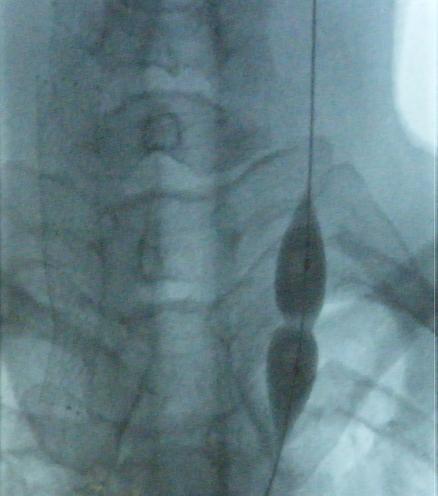

In 2009, Paolo Zamboni, an Italian researcher, offered hope in his finding an association between MS and compromised drainage of blood, from the brain. The responsible veins were malformed, creating what he termed chronic cerebrospinal venous insufficiency (CCSVI). In a small trial, he corrected the malformation of these veins using a balloon, with only a needle puncture. The technique is identical to that used by physicians every day to open coronary arteries. And some patients got better. Of course, it is hard to really tell better in a disease that comes and goes, like MS. But it did offer hope for many in the MS community. I know that because as a vascular surgeon I got calls from patients asking to have the procedure, a percutaneous venous angioplasty.